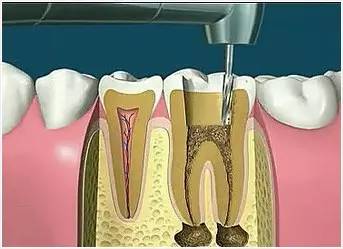

2、揭開髓腔

去凈腐質(zhì)和原有充填物、揭凈隨頂,看到整個髓底解剖結(jié)構(gòu)以便后續(xù)治療順利進(jìn)行。

4、根管預(yù)備

根管清理成形的目的是去凈根管壁上的感染物,通過根管器械的切削作用去除感染的牙本質(zhì)并清理根管壁細(xì)菌以利于根管充填。